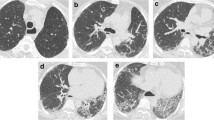

The readout was performed by two radiologists (T.F. 16 and K.M. 5 years of experience in thoracic imaging) by consensus: If there was disagreement between the two readers, whether an HRCT feature was present or not, re-assessment was performed until consensus was reached. Images where evaluated for the presence of characteristic visual ILD features (yes/no) including pulmonary emphysema, honeycombing, subpleural lines, pleural margins, bronchiectasis, ground-glass opacities, and reticular changes (Fig. 1). A case-by-case evaluation was performed.

For detailed information and distribution of the features among GAP stages, please refer to Table 1 and Fig. 2.

Varying grades of fibrosis within the same GAP stages. Patients with a, b GAP stage 1 and c, d GAP stage 2. a A 43-year-old female patient with GAP1 shows subpleural reticulations, subpleural lines, and some ground-glass opacification—overall less than 10% of fibrosis. b A 56-year-old female patient with GAP1 shows basal and subpleural reticulations, ground-glass opacities, and subpleural lines accounting for more than 20% of lung fibrosis. c A 69-year-old female patient with GAP2 shows only discrete subpleural lines. No other signs of fibrosis are visualized. d An 80-year-old male patient with GAP2 showing subpleural reticulations accompanied by ground-glass opacification, subpleural lines, and pleural margins in the right lung